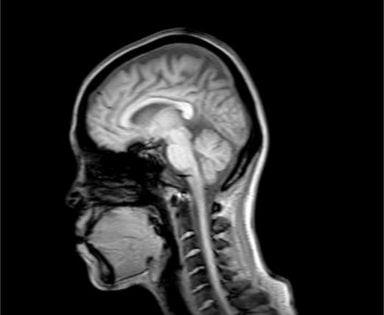

パニック症状は扁桃体が重要な役割を担っていると考えられている。

視床や感覚皮質を通った環境からの入力刺激や前頭皮質や海馬などに蓄積された経験を仲介する。

さまざまな部位を刺激することによって、不安やパニック症状を引き起こすと考えられている。

中脳水道周囲灰白質は特に重要であると考えられる。